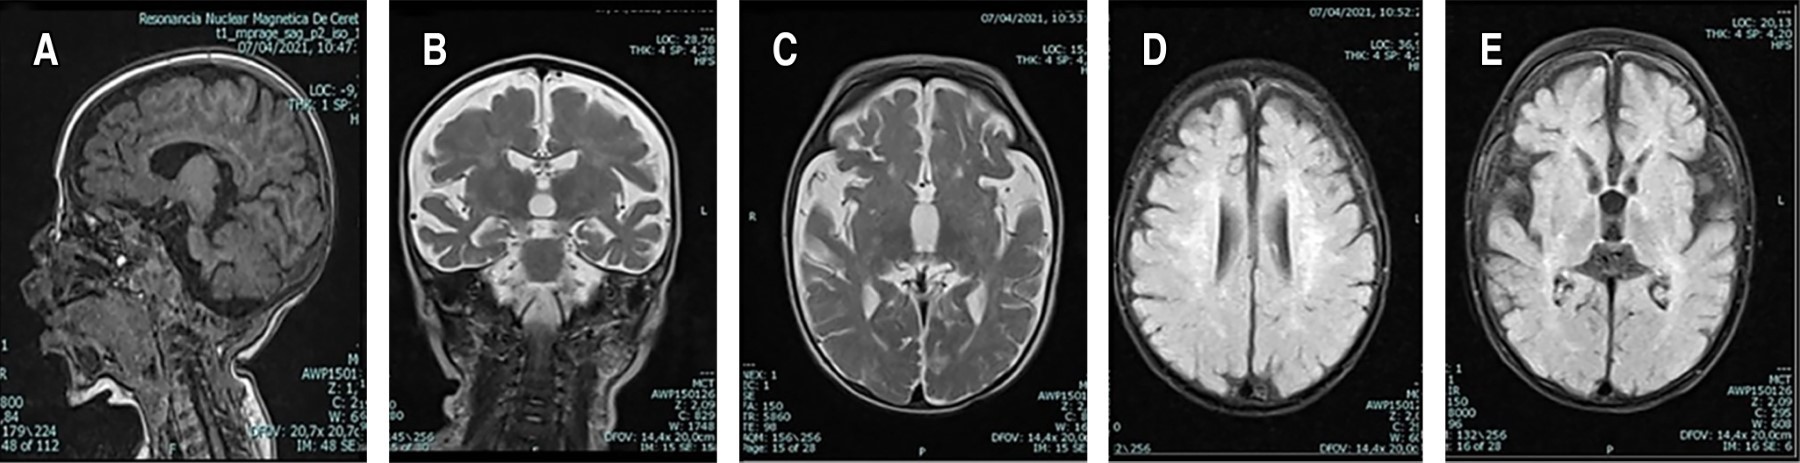

Se descartó neuroinfección y se suspendió el esquema antimicrobiano. Se realizó RMC, cuyas imágenes se presentan en la Figura 2. También se realizó electroencefalograma por presencia de posturas anormales persistentes, en el cual se reportó lentificación moderada de los ritmos de fondo, posiblemente relacionados con el uso de medicamentos (benzodiacepinas o barbitúricos), pero sin actividad ictal.

Existen diferencias relacionadas con la edad en la RMC, especialmente entre los fenotipos infantil temprano, de inicio tardío y adolescente/adulto. En las formas infantiles hay aumento de la intensidad de la señal T2 en la sustancia blanca cerebral, el núcleo dentado y la sustancia blanca cerebelosa. En la enfermedad del adulto hay aumento de la intensidad de la señal T2 en las regiones parietooccipital y los tractos corticoespinales; los núcleos dentados y la sustancia blanca cerebelosa generalmente se conservan.26 La disminución significativa de la velocidad de conducción motora y sensitiva es una clave valiosa hacia el diagnóstico, como lo fue en nuestro caso.27